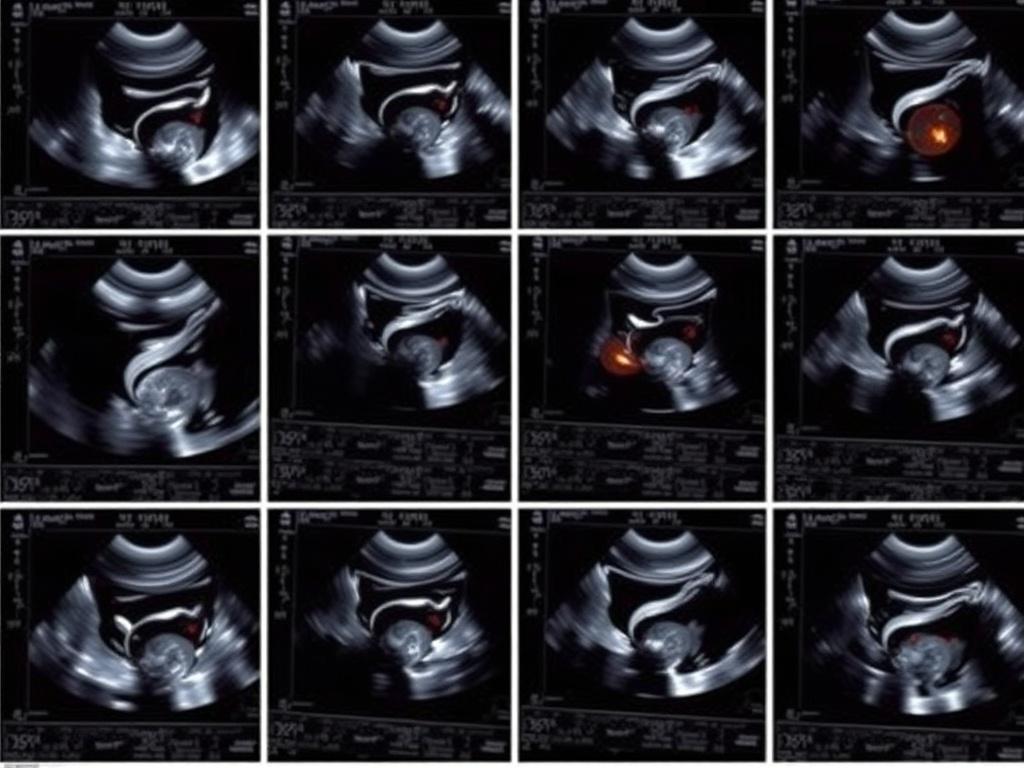

Еще один аспект — использование примеров и иллюстраций. В протоколах часто встречаются изображения и клинические случаи. Важно, чтобы эти материалы были анонимизированы и не позволяли идентифицировать пациента. Хороший онлайн‑сборник предусматривает механизмы редактирования и защиты визуальных материалов, чтобы сохранить этическую сторону исследования.